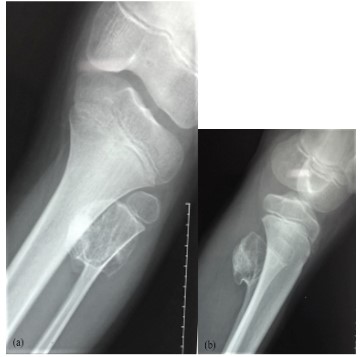

Knee x-ray showed a pedenculated tumor developing from the fibula neck (Figure 1a, 1b) increased in size compared with previous radiographs (Figure 2a, 2b). CT confirm findings with this “cauliflower like” exestosis developing from fibula neck with cartilage cap and with no invasion of the cortical bone (Figure 3).

Figure 2: (a,b) increasing in osteochodroma size extending postero-medially.